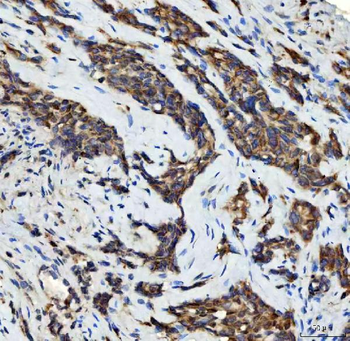

50 μl, 100 μl, 200 μlTIG2 Rabbit Polyclonal Antibody [orb11481]

IF, IHC-Fr, IHC-P

Human, Mouse, Rabbit

Human, Mouse, Rabbit, Rat

Rabbit

Polyclonal

Unconjugated

50 μl, 100 μl, 200 μlAnti-Aurora A/AURKA Antibody [orb1290027]